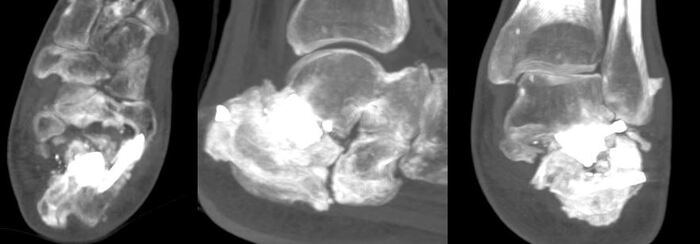

Результаты КТ, которые демонстрируют отсутствие консолидации подтаранного сустава(анкилоза), наличие металлоконструкций (пористый титан, скобы и винты). А также наличие выраженной деформации пяточной кости.

Итого имеем: отсутствие сформированного анкилоза после артродеза, сохранение грубой деформации пяточной кости, наличие металлоконструкции и дополнительной рубцовой ткани от предшествующего хирургического вмешательства.